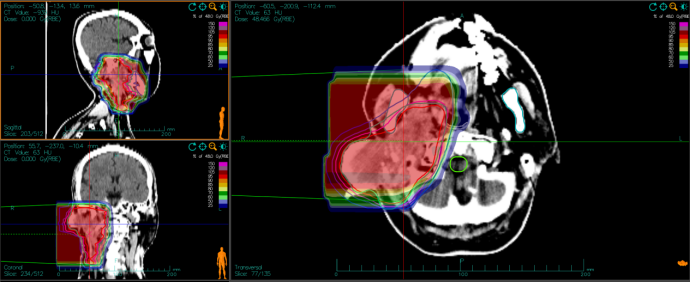

Fig.2 The image of the dose distribution of carbon ion radiotherapy of Case 1.

Primary tumor volume (GTV) included tumor lesions shown by enhanced MRI and/or PET/CT examination, including retropharyngeal lymph nodes.GTVnd for neck metastatic lymph nodes, outlining for neck metastatic lymph nodes shown by enhanced MRI and/or PET/CT examination. The planned target volume, PTVboost, was defined as a 5-mm expansion in all directions on the basis of GTV and GTVnd. Clinical target volume (CTV) included GTV+3-5 mm and the extent of subclinical foci based on the surgical and histopathological reports and MRI or enhanced CT images, and determined according to the biological behavior of the tumor. adenoid cystic carcinoma is prone to invade along the nerves, so it should include the sites of the tumors nerves and their pathways up to the skull base or intracranial. Prophylactic irradiation of the lymph node drainage area is not routinely performed, and in patients with pre-existing cervical lymph node metastases, prophylactic irradiation of the lymph node drainage area in that region is required. The planned target volume PTV was defined as a CTV based on a 3-mm flare in all directions, taking into account organ motion and posing errors. Segmental dosing was used to calculate the dose distribution of carbon ion passive beam uniform scanning irradiation using ci-Plan, with the first course of planned PTV-Boost: 8-12 Gy(RBE)/2-3 Fx, and the second course of PTV: 54 Gy(RBE)/14 Fx. The prescribed dose to the tumor for the five patients ranged from 64.0 to 68 Gy(RBE)/16 to 17 Fx. Carbon Ion doses are expressed as Gy(RBE), defined as the physical dose multiplied by the carbon ion RBE, all at a relative biological effectiveness (RBE) of 3.0. Carbon ion endangered organ limits refer to the dose limits of each endangered organ for ion therapy throughout the body [10], brainstem Dmax < 45 Gy (RBE), D1 ≤ 38.5 Gy (RBE); crystalline D1 < 6 Gy (RBE); optic pathway D20 < 30 Gy (RBE); spinal cord Dmax < 30 Gy (RBE), D1 ≤ 31.5 Gy (RBE); parotid gland Dmean < 21 Gy (RBE) (bilateral), Dmean < 18 Gy (RBE) (unilateral).